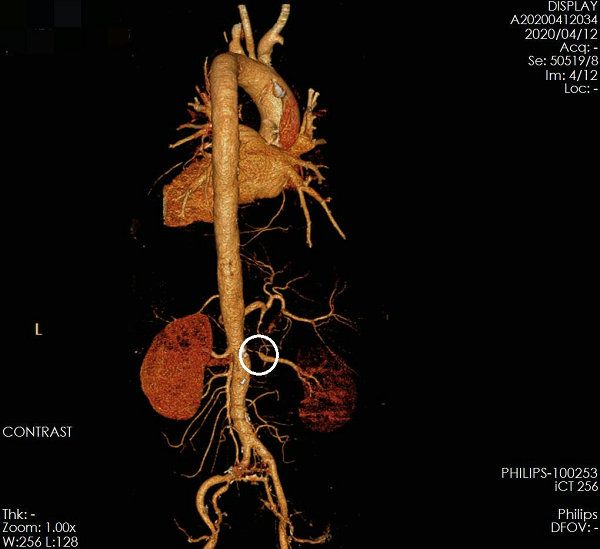

来到五附院后,值班大夫赶紧带他做了个胸腹主动脉CTA,结果确诊胸主动脉夹层,血管内膜从左侧锁骨下动脉以远一直撕到右侧髂动脉,幸运的是夹层大部分假腔已经大部分血栓化,但是仍有破口血流进入,而且没有影响重要的内脏动脉。CTA检查还发现了一个关键问题,右侧肾动脉重度狭窄,患者高血压考虑为继发性高血压,平日血压控制不好极有可能是这个原因。

▲ 图2 术前CTA右侧肾动脉重度狭窄,右侧肾脏显影明显较左侧浅淡